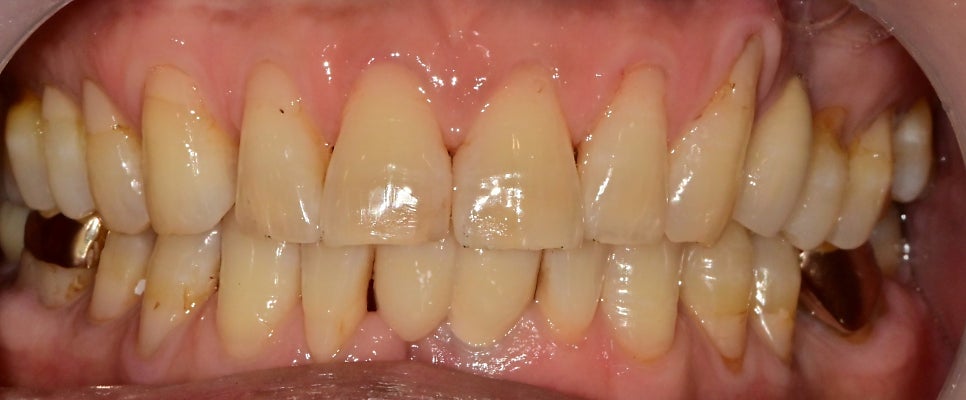

아래 앞니 쪽이 잇몸이 자주 붓는다고

내원해 주셨습니다.

2개의 치아가 치주염으로 인한 치조골 소실로

치아 이동이 일어나 공간이 벌어져있었습니다.

수술 후 직후의 모습입니다.

앞니 임플란트의 수술 즉시 임시치아는

씹는 용도가 아니고 빈 공간을 채워주는 것이 목적이기

때문에 위 치아와 교합을 조정해 주고 잇몸 경계에 맞춰

임시치아를 수정했습니다.

물론 최종 보철물처럼 색상을 다 맞출 순 없지만

뺐다 꼈다 하는 임시틀니를 끼는 것보다는 훨씬

자연스럽다고 말씀해 주십니다.